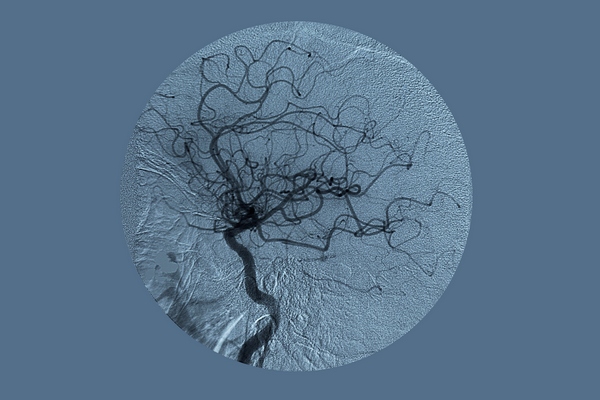

Цікаво знаходити схожі утворення в мікро-і макросвіті. Надихати може й те, що геометрію цих утворень наука може описати. Кровоносна система, річка, блискавка, гілки дерев… все це — схожі системи, що складаються з різних часточок і мають різний масштаб.

Дерева, блискавка, бронхи і кровоносна система людини мають фрактальну форму, ідеальними природними ілюстраціями фракталів називають також папороті та капусту брокколі. «Все так складно, все так просто» влаштовано в природі, помічають люди, з повагою прислухаючись до неї.